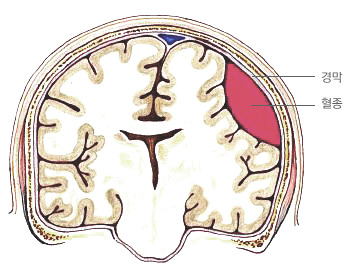

급성 경막하 출혈 acute subdural hemorrhage

급성 경막하 출혈은 뇌를 둘러싸고 있는 경막(dura)이라는 막의 안쪽에서 뇌 표면의 혈관이나 뇌와 경막 사이를 이어주는 혈관이 외상에 의해 파열되어 다량의 급성 출혈이 발생하여 뇌와 경막 사의의 경막하 공간(subdural space)에 피가 고여 뇌를 압박하는 상태로서, 흔히 뇌 실질의 좌상(타박상)과 파열, 뇌내출혈을 동반한다.

뇌 전산화 단층촬영으로 급성 경막하 출혈을 진단하고 동시에 뇌 실질에 좌상(타박상), 열상(찢어짐), 뇌내출혈 등이 동반되어 있는지 확인할 수 있다. 또한 뇌 부종의 정도와 뇌가 압박을 받는 정도를 확인할 수 있으므로 환자의 상태를 이해하고 치료방침을 정하는데 매우 중요하다.